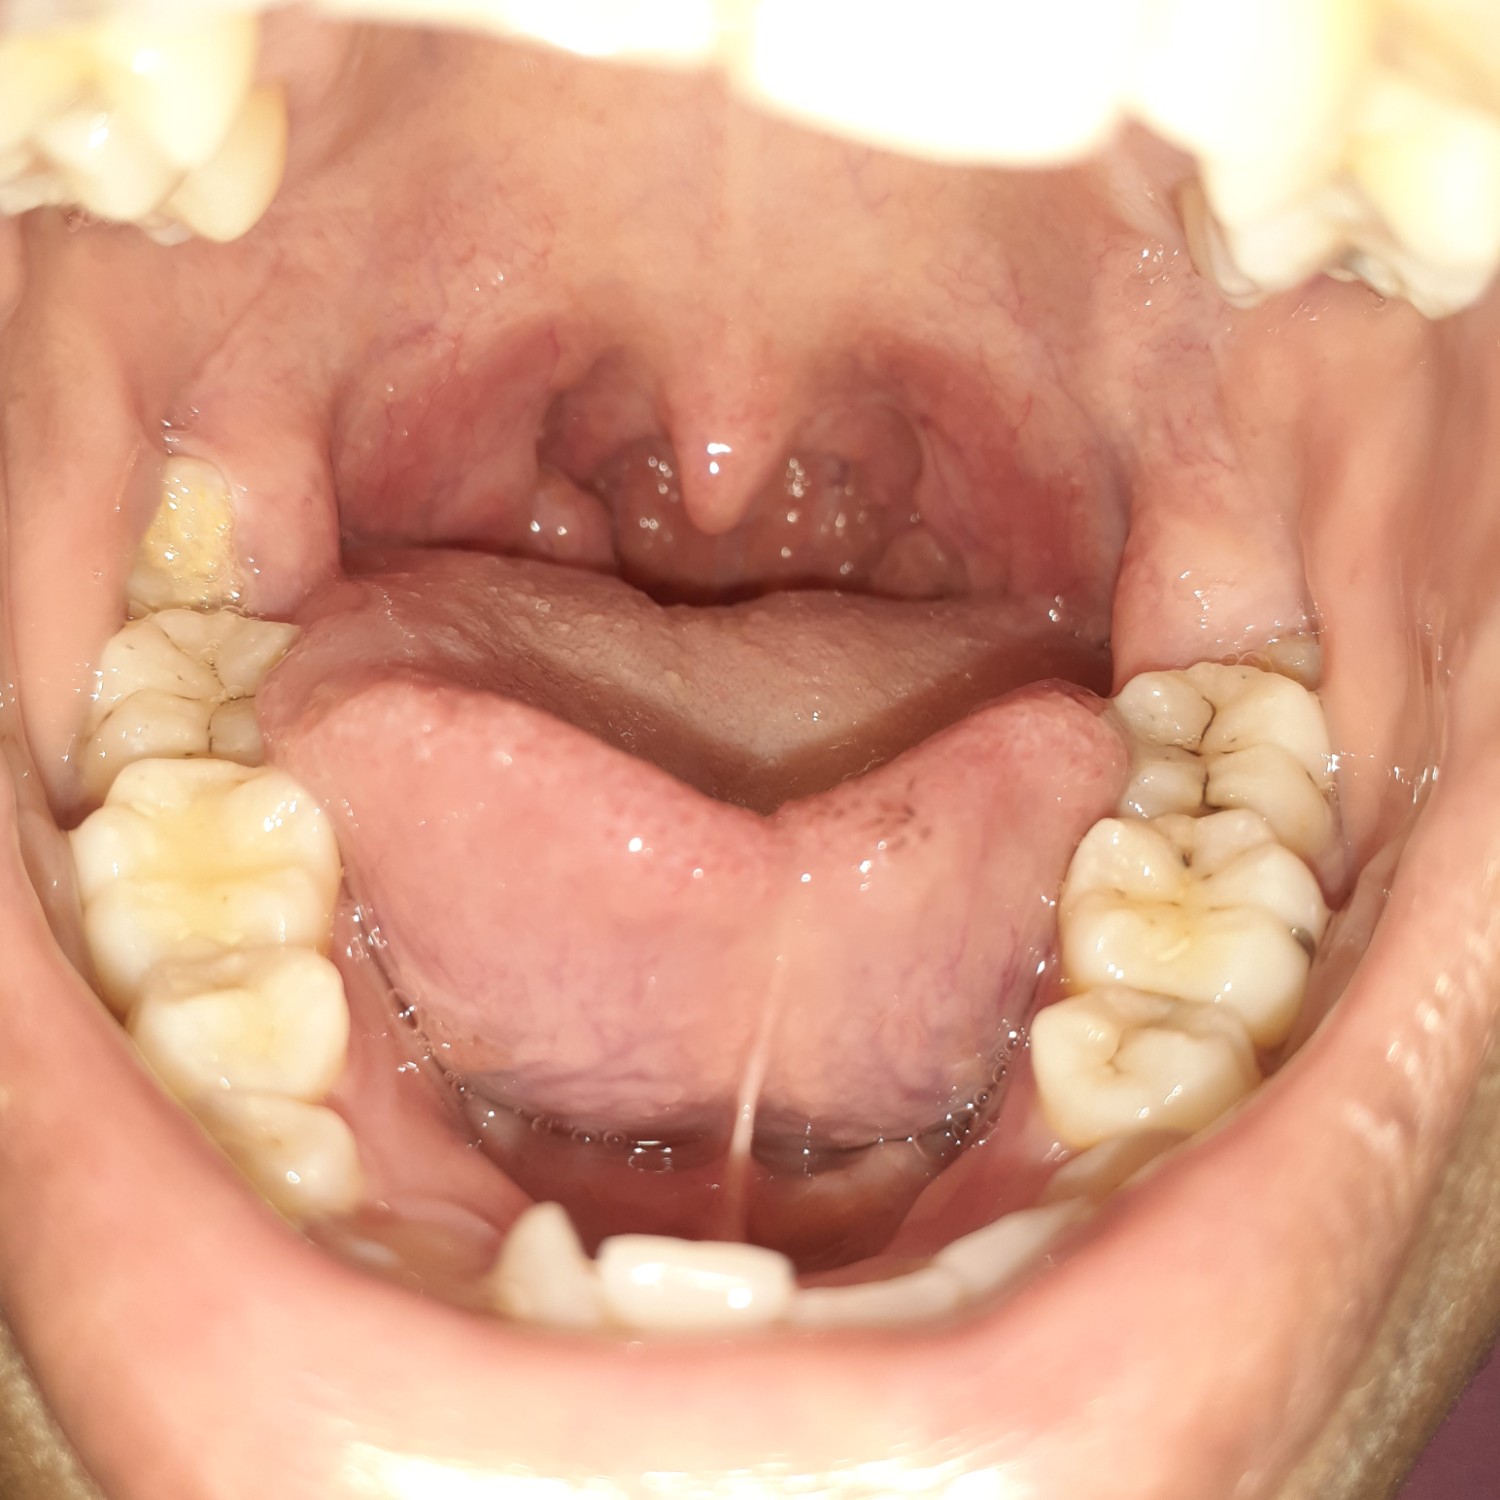

คอเป็นแบบนี้ปกติมั้ยค่ะ